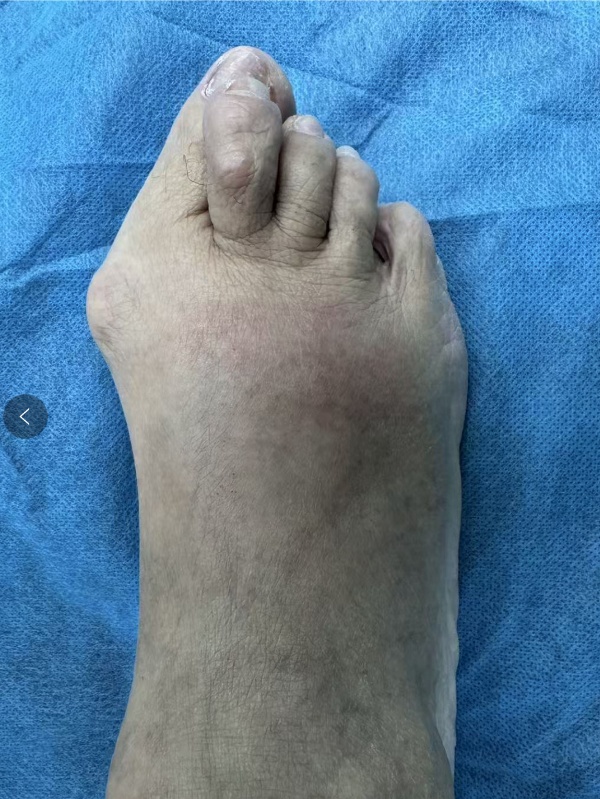

77岁的李奶奶(化名)受拇外翻困扰已有三十多年。随着畸形加重,大脚趾严重挤压第二趾,形成了典型的“叠趾畸形”。长期的摩擦疼痛让她每走一步都钻心地疼。

图注:术前检查:明显的第1跖趾关节外翻,伴随第2趾受压形成的“叠趾畸形”